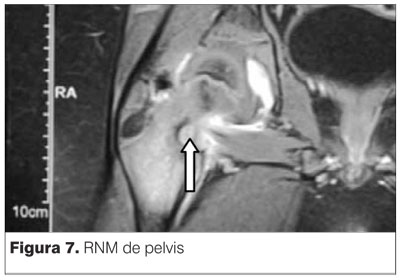

RNM informa asimetría en T2. Se observa claramente la lesión tumoral apoyada sobre la cortical posterior del cuello de fémur derecho (figuras 6, 7 y 8).